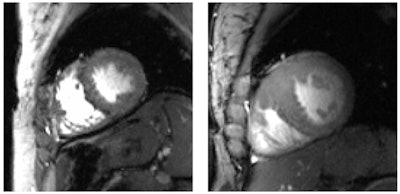

High-resolution short-axis views of the heart acquired at 7 tesla of a healthy subject (left) and a patient with hypertrophic cardiomyopathy (right).Ultrahigh-field cardiac MRI provides "an unprecedented potential for real-time imaging and addressing some of the shortcomings and physiological constraints of traditional assessments of left ventricular and right ventricular structure and function," noted the authors, citing "accelerated imaging capabilities of free-breathing real-time imaging" of the heart at 7 tesla.